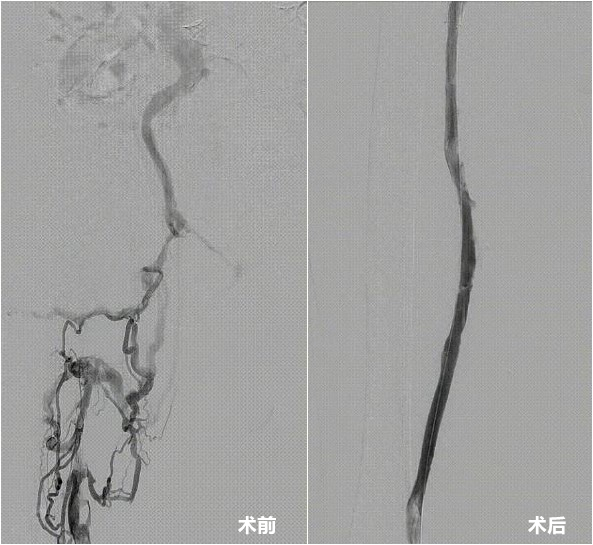

患者术前术后下肢静脉造影对比。

经造影显示,赵爷爷的右下肢已有多条静脉节段性血栓形成,而且血栓不仅在腿部蔓延,还一直向上长进了髂静脉(位于盆腔内深部的大血管)。“血栓把人体的大静脉完全堵塞了,就好比主干道严重堵车,只有小路能通行,血管梗阻的严重程度可想而知,老人急需手术将血栓取出。”华体会体育 血管外科主任庄晖表示,如不及时处理,将严重影响患者今后生活质量,可能会引起反复的下肢麻木、肿胀,甚至溃烂、坏疽等下肢血栓栓塞后遗症,急性肺栓塞等致死性并发症的可能性也大大增加。

经全面评估,华体会体育 血管外科团队决定采用参与研发的国内首款专门为下肢静脉血栓治疗设计的取栓系统开展手术。术中,细小的导管精准抵达栓塞部位,凭借独特的结构设计高效抽吸,如同“血管清道夫”一般,快速清除了大量新鲜与顽固的陈旧血栓。反复操作确认血管畅通无阻后,赵爷爷堵塞已久的“生命通道”终于重建。同日,庄晖团队运用同一器械,再次成功救治另一名70岁高龄的复杂血栓患者。相比传统治疗方式,新器械手术时间短、取栓效率高,降低了血管内膜损伤和出血并发症的风险,为患者(尤其是高龄、危重患者)提供了更优解。